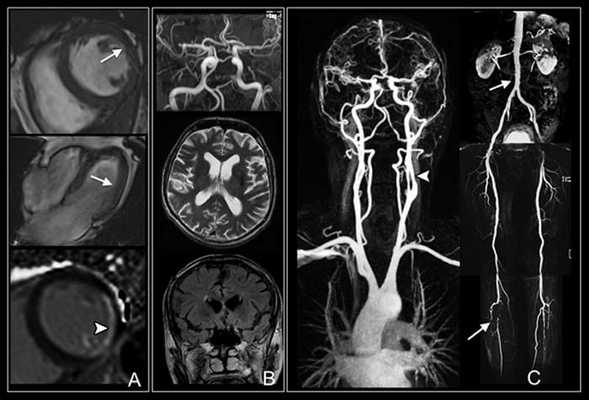

КТ снимки сосудов шеи

КТ-ангиография сосудов шеи с контрастом - золотой стандарт диагностики, но чтобы получить максимальную пользу от исследования, необходима слаженная работа профессионалов. Расшифровкой результатов занимается рентгенолог. В центре “Магнит” в Санкт-Петербурге КТА - одна из востребованных процедур, а наши врачи ответят на любые вопросы. В сложных случаях оценка томограмм проводится коллегиально. Представляем Вашему вниманию несколько томограмм, где четко видны патологические изменения:

КТ-ангиограмма кровеносных сосудов в области шеи. Позвоночная артерия находится между вертикальными линиями. Стрелка указывает на позвоночник

3D-изображения компьютерной мультиспиральной томографии Виллизиева круга. Его контуры можно увидеть на томограмме в центре, шея внизу, основные артерии белого цвета.

Коронарное изображение МСКТ демонстрирует саккулярный затек контраста (толстая стрелка) из правой внутренней сонной артерии (псевдоаневризма). Левая сонная артерия (тонкая стрелка) не повреждена.